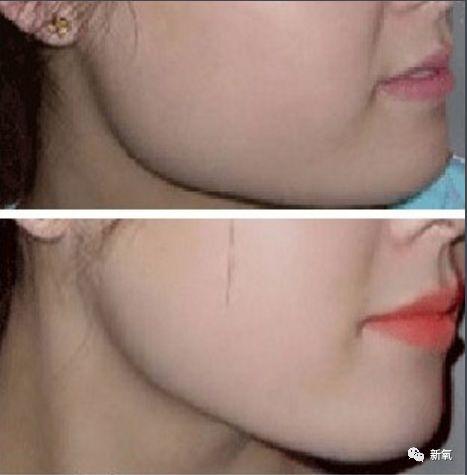

可是如果在面部各处还在发育的时候就进行干预,牙齿、骨骼的改建能力极强,一些颌骨发育问题就可以被改善。最终实现不动骨改变颌面骨骼的目的。

看下面这个真人案例,仅在整牙的矫正下,不仅下牙列回到正常的位置,连原本被限制发育、显得凹陷的中面部也变得正常,明显侧脸变得饱满了。

如果错过这个时期,骨骼全部定型后想要矫正这个问题,就只能动骨了···

而且仅将下颌骨推进去也无法让上颌再长出来,也就意味着:之后还需要将受到影响发育不足的鼻基底、鼻子补起来。(注意看右边的鼻基底和上颌依然是扁平的)